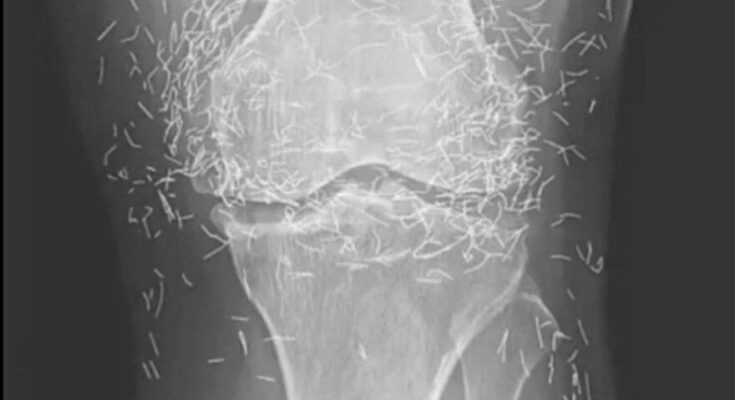

Years later, when doctors took X-rays to evaluate her knee condition, they weren’t prepared for what appeared on the images. Her knees were filled with dozens of bright, metallic flecks — tiny needles embedded deep within the joint area.

The findings were later documented in a case published by the New England Journal of Medicine.

Beyond inflammation, the needles created another problem: imaging complications. Metal objects can obscure parts of the anatomy on X-rays, making it harder for doctors to clearly assess joint damage or disease progression.